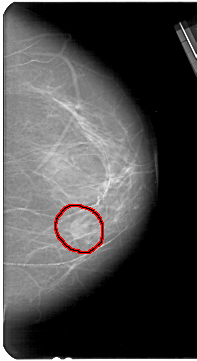

A_1681_1.LEFT_MLO

LEFT_MLO LINES 5491 PIXELS_PER_LINE 3526 BITS_PER_PIXEL 12 RESOLUTION 43.5 NON_OVERLAY

FILE: A_1681_1.RIGHT_CC.OVERLAY

TOTAL_ABNORMALITIES 1

ABNORMALITY 1

LESION_TYPE MASS SHAPE ROUND MARGINS ILL_DEFINED

ASSESSMENT 4

SUBTLETY 3

PATHOLOGY BENIGN

TOTAL_OUTLINES 1

BOUNDARY